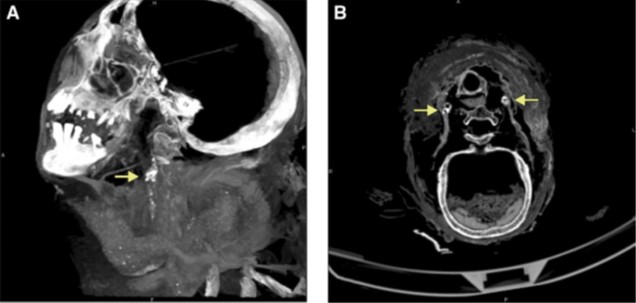

Se invece il dolore è intorno alle spalle e le dita tremano, secondo il papiro è “una secrezione” (o “ghiandole ingrossate”) da combattere facendo vomitare il paziente con “pesce nella birra” e con carne o pianta “djs” (sconosciuta anch’essa finora) legando le sue dita con i viticci della cosiddetta zucca-bottiglia (Lagenaria siceraria), dopo di che “il paziente starà meglio”.

Se da un lato ci può far sorridere l’approccio medico, è sorprendente come fossero già riconosciute le proprietà terapeutiche di alcune sostanze e la loro applicazione. Vedremo invece nelle pratiche chirurgiche il trattamento degli aneurismi.